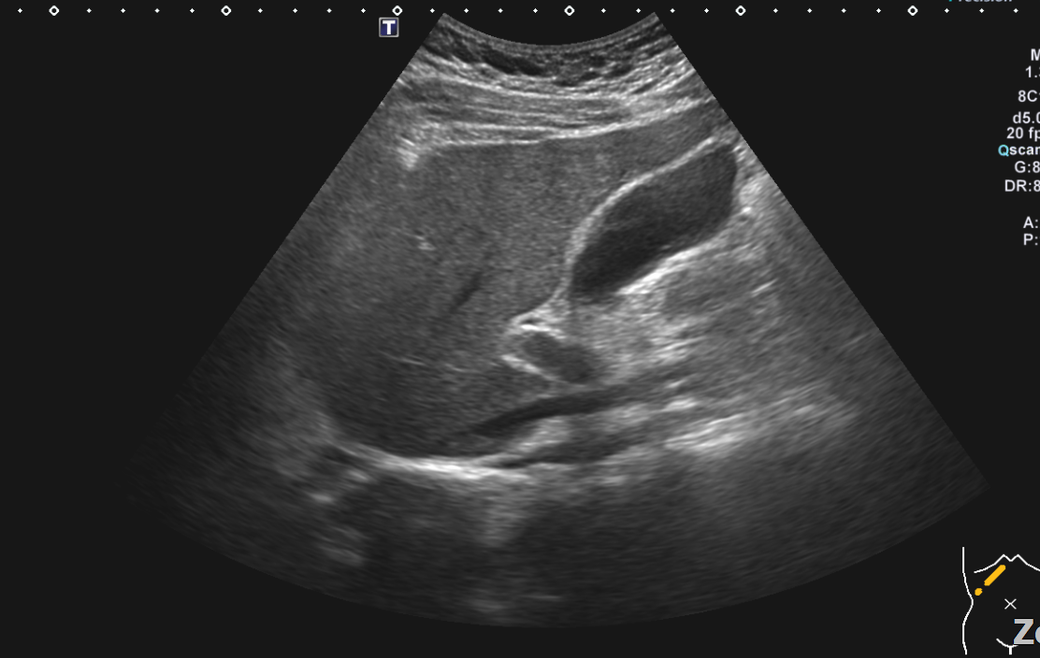

복부초음파 신장 물혹 보이나요? 사진올려봐요

신장물혹 0.6cm mri에는 나오는데 복부초음파에는 소견이없어서요

• 2번 째 사진

올려주신 사진 중 우측 신장이 찍힌 영상은 한 장이며 단면 영상만으로는 물혹 유무를 확인할 수 없습니다.